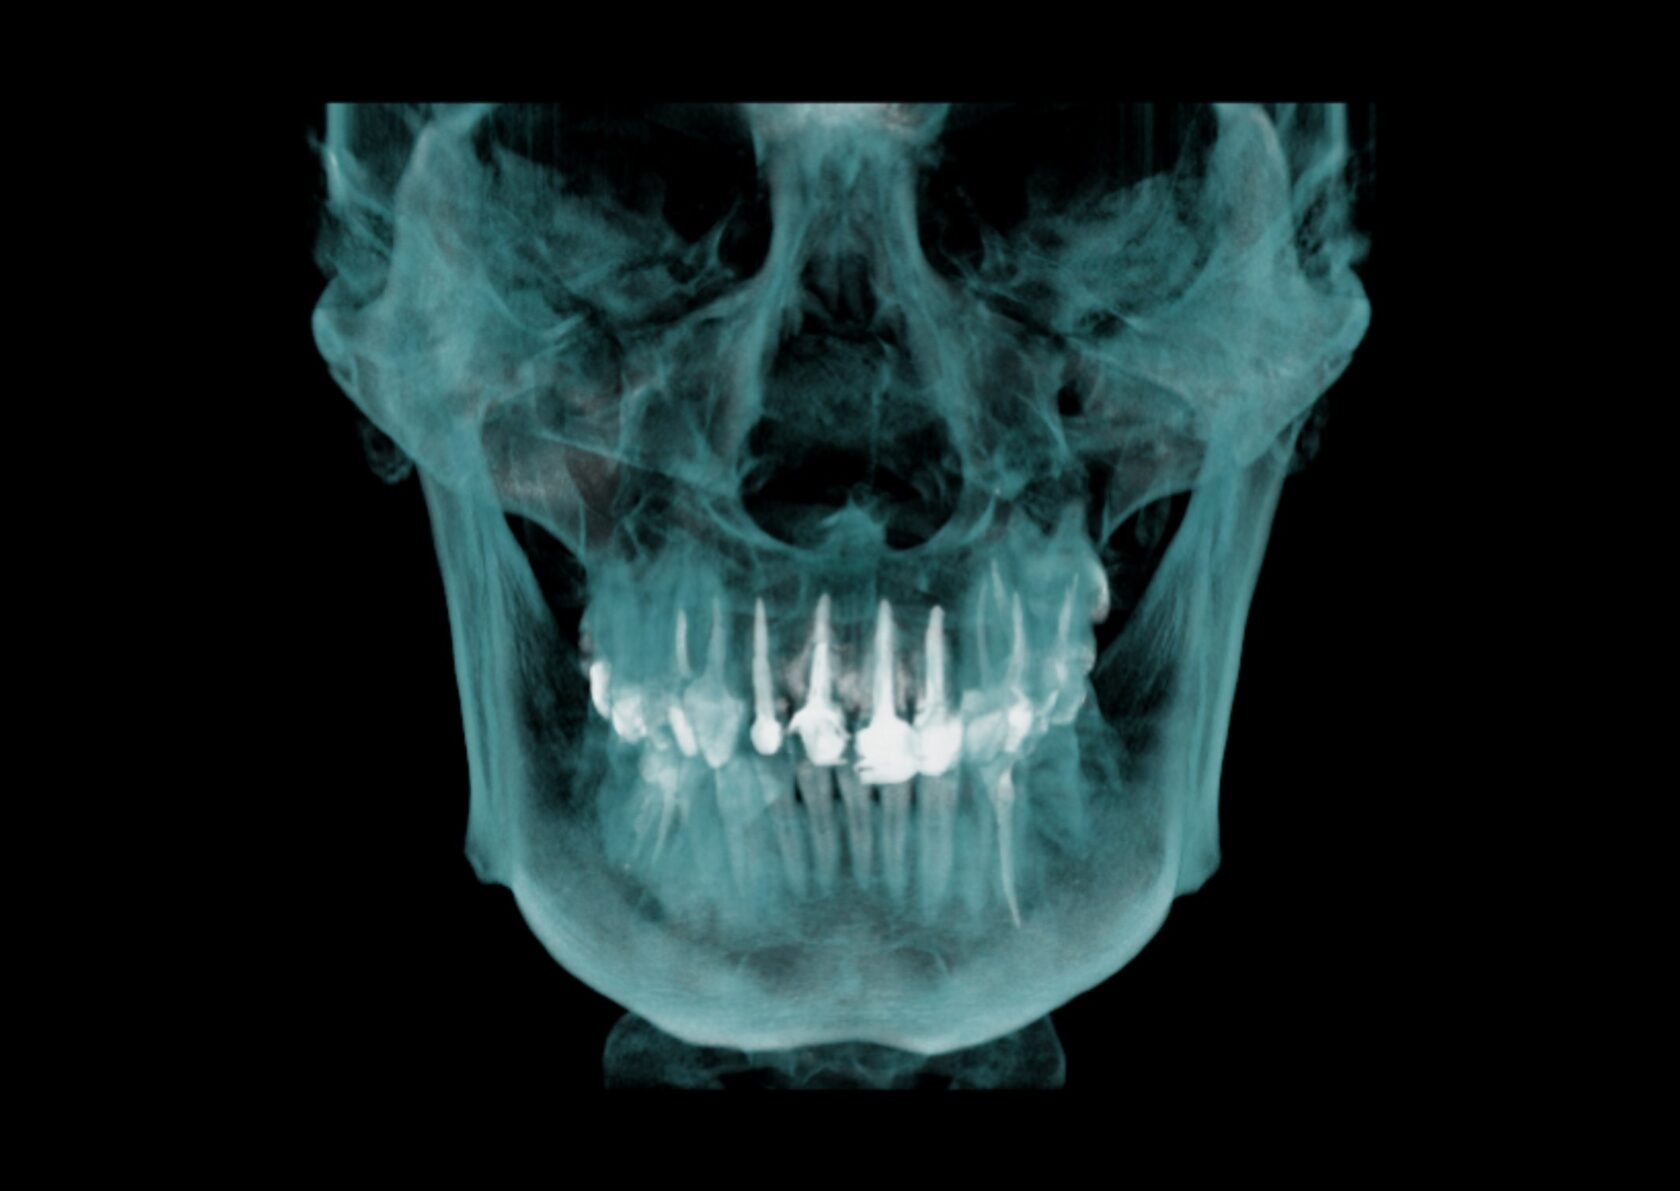

Оценка нижней, верхней челюсти, области ВНЧС, верхнечелюстных пазух и ротоглотки.

Планирование лечения с захватом нижней части гайморовых (верхнечелюстных) пазух, области третьих моляров - идеально для любых амбулаторных вмешательств.